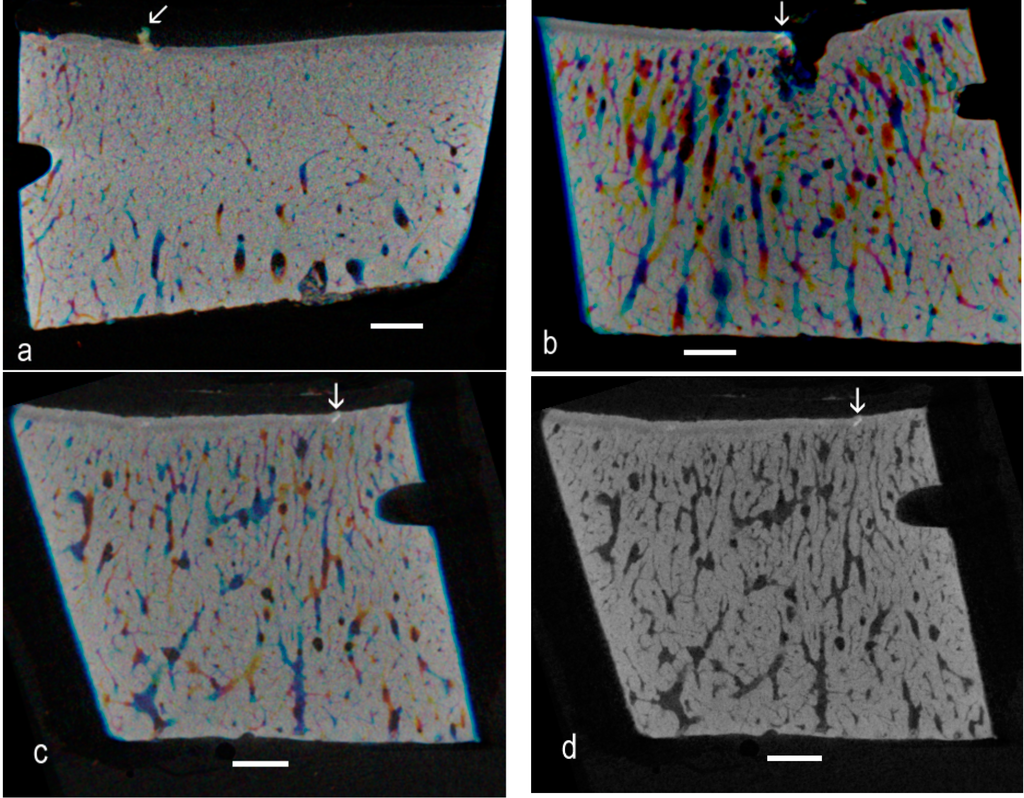

Successive images can be displayed as red, green and blue components in a composite image, when matching brighter patches show as white against a colored background. Likewise, images can be averaged over depths of, say, 2, 3 or 4 original Z levels, and these averaged images are assigned as R, G and B components in a composite image (Figure 3a–c). Another simple strategy for spotting high-density patches is to use image arithmetic to look for the darkest regions in a grey level Z series (Figure 3d).

Figure 3. (a) Successive eight-bit grey level images (averages of two original Z levels) images assigned as Red, Green and Blue: matching brighter patches show as whiter against a colored background. Advanced OA, seven-year-old; (b) From sample from an eight-year-old that showed the highest number of easily-spotted HDMI fields in a control sample. Successive averages of four grey level images displayed as R, G and B components in a composite image; (c) Another region from the same sample; six sequential Z planes summed in pairs, then pairs displayed as RGB components; and (d) Same six planes processed to retain the darkest pixels.